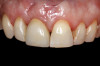

4. Facial and occlusal views of initial clinical presentation of tooth No. 8.

Figure 4

5. Facial and occlusal views of initial clinical presentation of tooth No. 8.

Figure 5